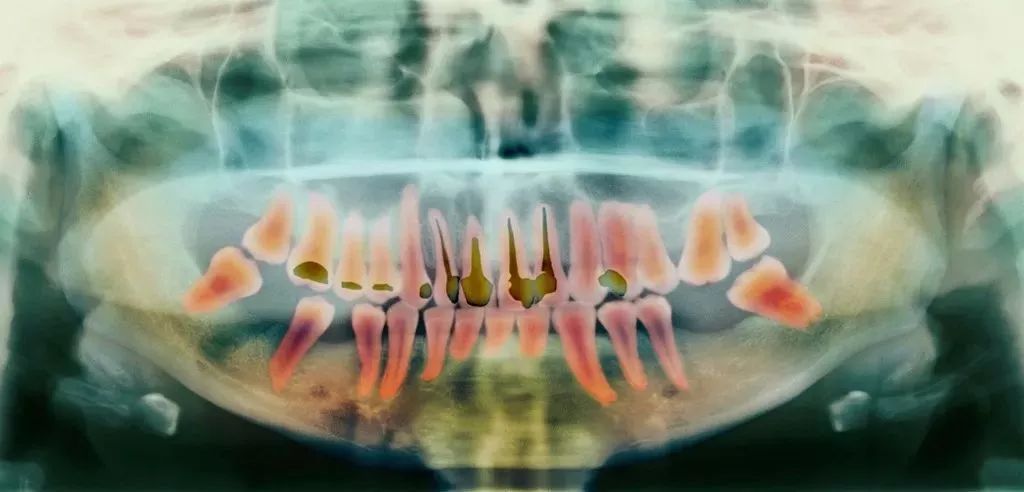

- 蛀牙坏到牙齿内部,牙髓或细菌感染引起了急/慢性牙髓炎;

- 牙髓由于长期刺激或其它原因造成的死髓牙;

- 意外磕碰、外伤,导致牙根尖血管断裂引起牙神经暴露;

前面就讲过了,当蛀牙才刚刚萌发的时候进行治疗,只需要简单补牙就可以解决了;但当蛀牙侵害到牙髓和神经,就不得不根管治疗了。

所以,如果蛀牙刚刚开始就被发现,就可以及时治疗,简单修复便无大碍了。

但是蛀牙初期发生的时候往往不会有任何感觉,如果你已经感觉到酸楚或者疼痛了,可能已经晚了,这个时候就不得不进行根管治疗,耗时耗力又费钱了。